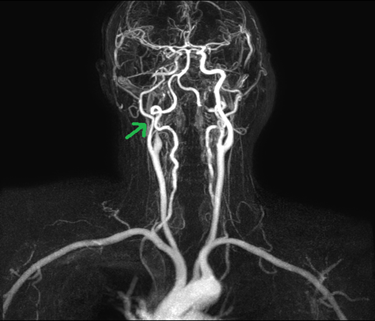

for further management. An mri head with angiogram (figure 2) was

performed which revealed acute right mca territory infarct in the region of

right insula, centrum semi-ovale and corona radiata in the right frontal lobe

and aneurysmal dilatation of the petrous segment of the right internal carotid

artery leading to possible occlusion of the right extracranial ica into the

petrous segment.

Figure 2: right ica

dissection on magnetic resonance angiogram (green arrow)